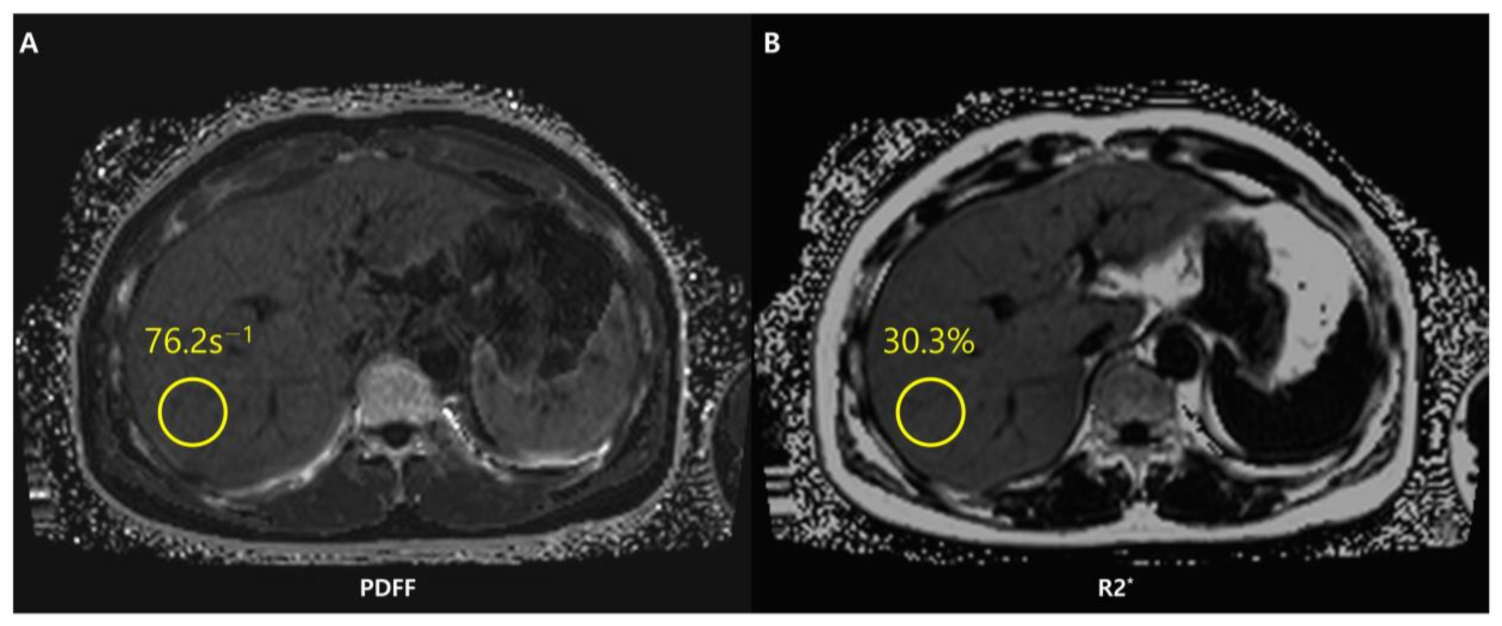

Chemical shift-encoded (CSE)-MRI separates fat and water signal components by recording spoiled gradient echoes at various echo times, often in one repetition [88]. CSE-MRI may be performed in a single breath-hold and may offer an almost real-time PDFF map reconstruction across the whole liver in about 15–20 s [76] (Figure 7).

In addition to evaluating hepatic steatosis, CSE-MRI allows simultaneous assessment of iron deposition. Iron is a paramagnetic substance and consequently reduces the T2* (i.e., increases the relaxation rate R2* as R2* = 1/T2*) and results in signal loss with an increase in echo time. The coexistence of fat and iron is relevant in conditions such as hepatocellular carcinoma, hemochromatosis, viral hepatitis, and hemosiderosis [93]. However, concomitant liver steatosis may hide R2* signal decay in the liver and confound the interpretation of iron deposition. With simultaneous estimation of PDFF and R2*, CSE-MRI offers fat-corrected R2* maps that allow liver quantification independently of the existence of fat [74,93]. Unlike other imaging methods such as conventional US or CT, CSE-MRI is therefore a useful imaging modality for fat and iron deposition that coexists in the liver. The characteristics, advantages, and limitations of conventional chemical shift images, MRS, and CSE-MRI are briefly shown in Table 1.

Figure 7. Chemical shift-encoded (CSE)-MRI allows an estimate of both fat in the liver and iron deposition simultaneously. Fat-corrected R2* mapping (A) is a standard byproduct of multi-echo CSE acquisitions used to map R2*-corrected proton density fat fraction (PDFF) (B). The system has detected a PDFF value of the ROI equal to 30.3%. The patient thus presents severe steatosis.